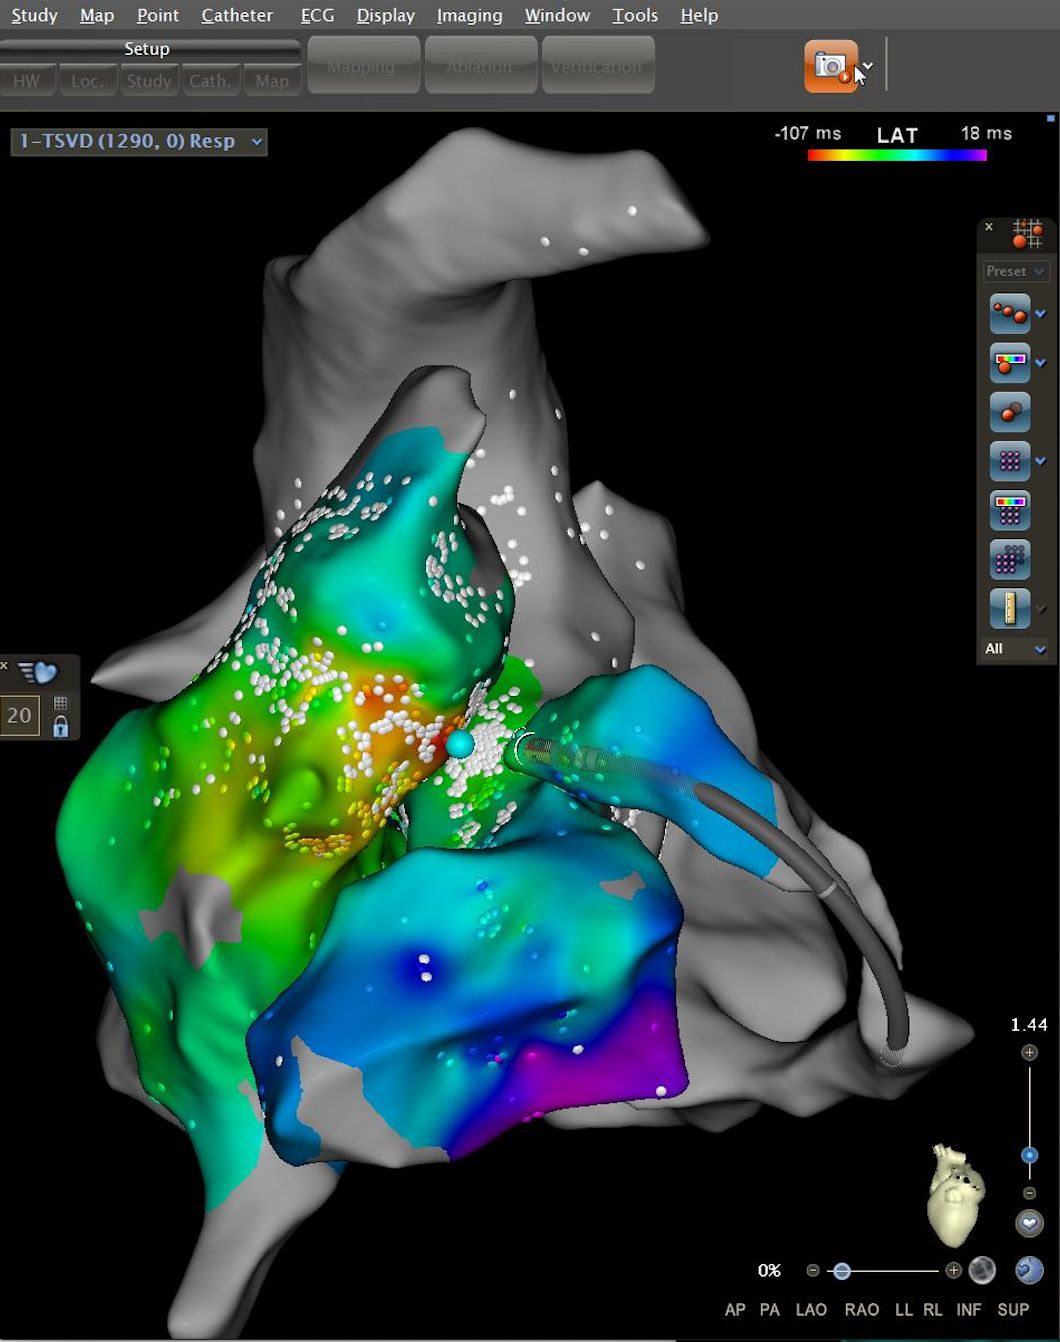

El Dr. Ernesto Díaz Infante (Sevilla, 1973) es un cardiólogo español reconocido en el campo de las arritmias cardiacas, muerte súbita y manejo de dispositivos de estimulación cardiacos (marcapasos, desfibriladores y resincronizadores cardiacos). Tiene una amplia experiencia en la ablación con cáteter de las arritmias más complejas, tanto fibrilación auricular, como taquicardia ventricular a nivel endo y epicárdico y arritmias en pacientes con cardiopatías congénitas complejas. Actualmente es el Director de la Unidad de Arritmias y Estimulación Cardiaca del Hospital Universitario Virgen Macarena de Sevilla, Profesor Asociado de Medicina en Sevilla y en la medicina privada es el Director de la Unidad de Arritmias del Hospital Vithas Nisa Sevilla.